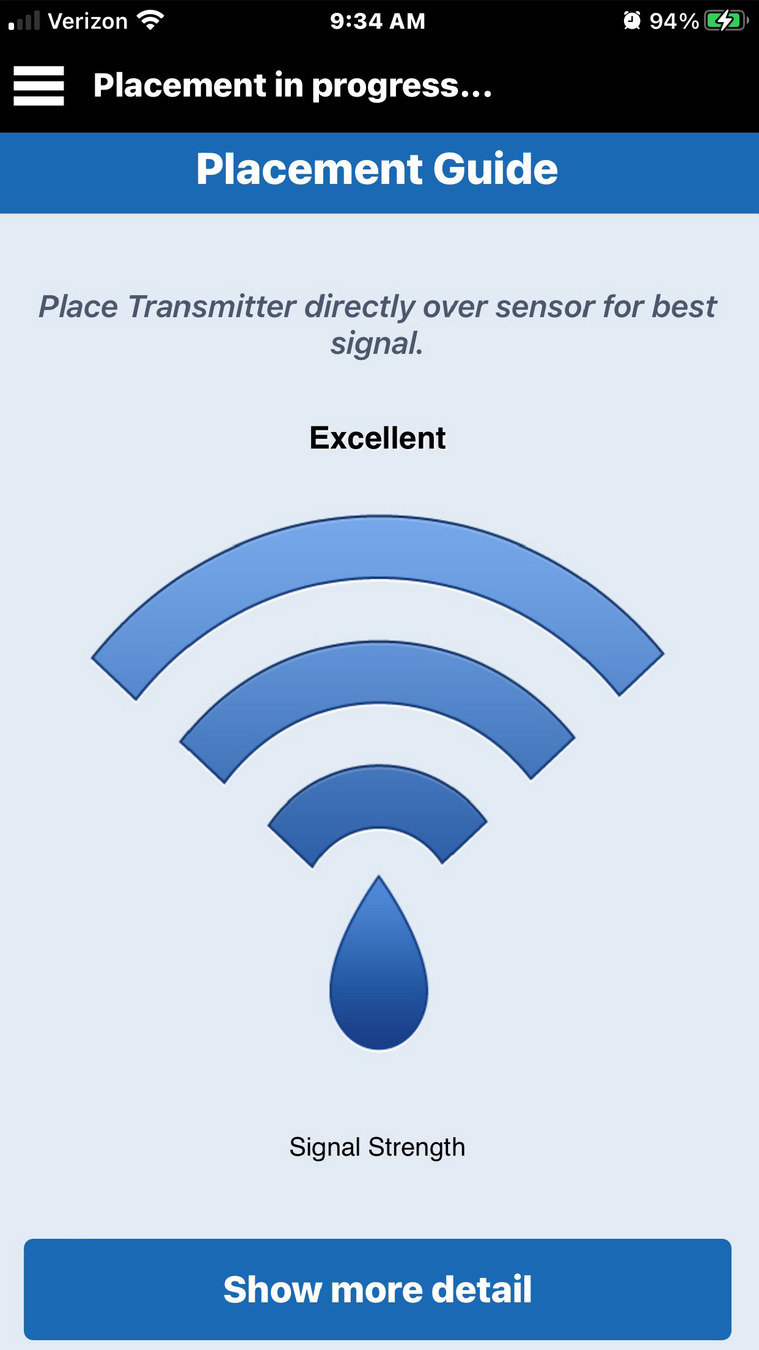

A continuación, abra la guía de colocación en la aplicación yendo al menú principal >

Guía de colocación.

A continuación, abra la guía de colocación en la aplicación yendo al menú principal >

Verá una X negra al principio.

Levante con suavidad y mueva ligeramente el transmisor inteligente junto con el adhesivo para encontrar la ubicación con la señal más fuerte, algún punto entre las 2-3 barras o de buena a excelente.

Puede ser de ayuda girar ligeramente el transmisor inteligente.

Cuando mueva el transmisor, deje que pasen unos segundos para que se actualice la señal antes de volver a moverlo.